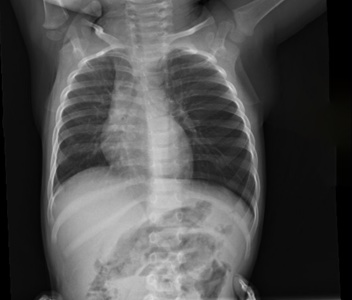

A 16 mo female is brought in by mom for intermittent cough and wheeze. Mom concerned because she said yesterday child's older brother left trail mix out and mom found patient with some in her mouth. Since then periodic cough and now wheeze today. No cyanosis or distress. AP and lateral decubitus xrays completed. What's the diagnosis? Scroll down for answer.

Answer: Non-radiopaque foreign body in left airway beyond the carina with hyper lucency of the left lung consistent with air trapping

- Air trapping seen on all views

- normally with decubitus xrays dependent lung collapses slightly, which is seen here on the right but not on the left

- patient taken to the OR with ENT and peanut was removed via bronchoscope from the left main stem bronchus, she was discharged the following day